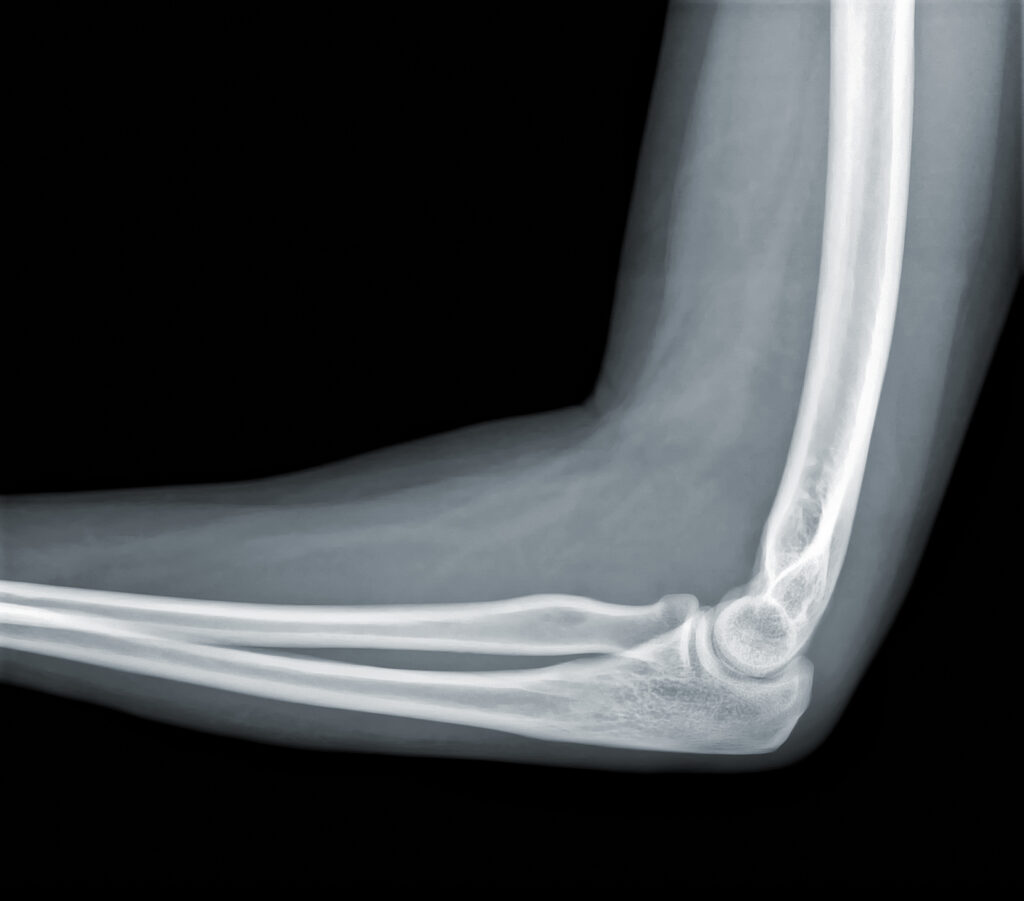

El rayos X de brazo es un estudio de diagnóstico por imagen que permite visualizar huesos como húmero, radio y cúbito.

La radiografía de brazo en Panamá es clave para detectar fracturas, fisuras o lesiones.

Tipos de Rayos X de Brazo

Radiografía AP y Lateral